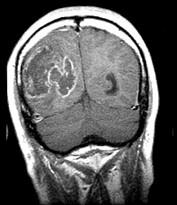

神经胶质瘤(如图所示)占全部颅内肿瘤的()A.20%~30%B.30%~40%C.40%~50%D.50%~55%E.>55%

问题 神经胶质瘤(如图所示)占全部颅内肿瘤的()

选项 A.20%~30% B.30%~40% C.40%~50% D.50%~55% E.>55%

答案 C